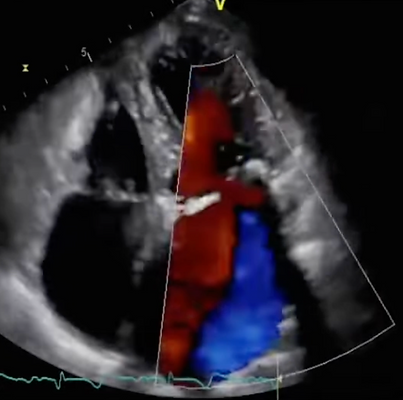

Echocardiogram – heart structure and function